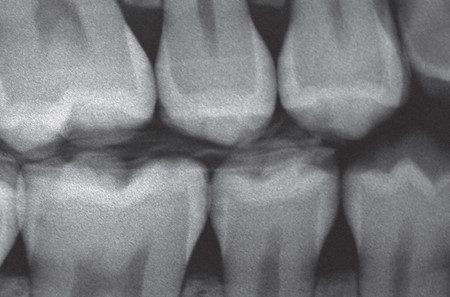

Hình 12. Sâu răng phía xa R35 được phát hiện khi chụp X quang và khám lâm sàng.

Hình 22. Hoàn tất phục hồi composite và kiểm tra X quang cho thấy sự tích hợp hài hòa giữa composite và cấu trúc răng ở vùng kẽ răng.